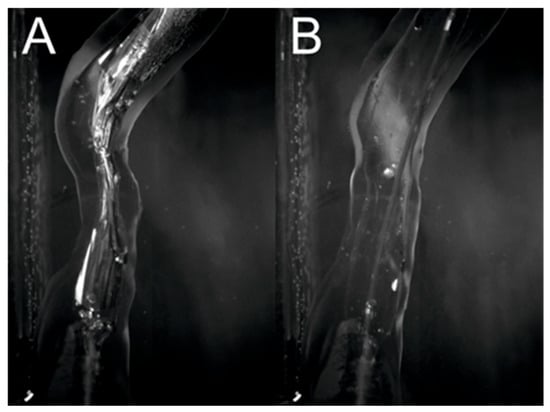

Figure 11 compares the artery models before and after balloon inflation. The measured inner diameter of the model was 2.13 mm before inflating the balloon and 4.05 mm after. The obtained dilation allowed the full lumen of the vessel with the inflated balloon to be reached. In addition, the vessel straightened as the balloon inflated, following the behavior of the vessel during an actual procedure. The obtained results prove that the printouts allow for high-quality pretreatment training by simulating the elastic properties of arteries, which is a valuable tool for doctors to reduce the risks associated with arterial angioplasty procedures in patients with atherosclerosis.

Figure 11.

Comparison of artery model before (A) and after (B) inflating the balloon.